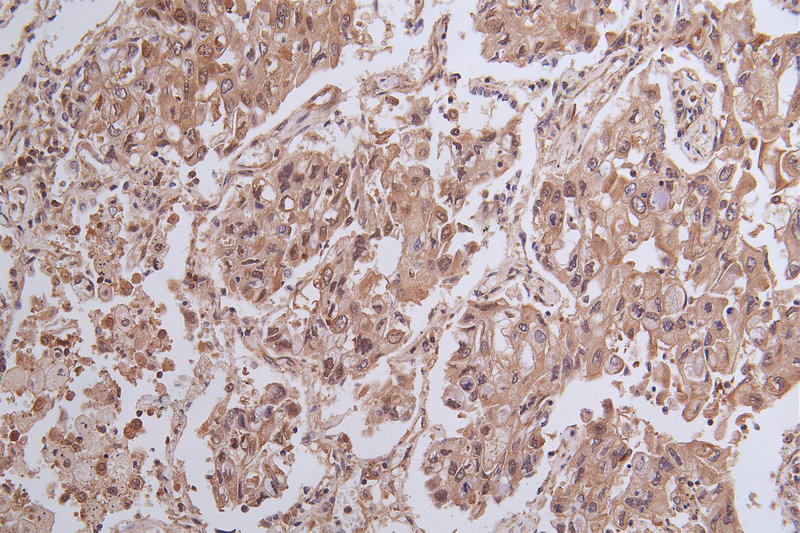

Immunohistochemistry of paraffin-embedded human ovarian cancer using CSB-PA026288LA01HU at dilution of 1:100

Immunohistochemistry of paraffin-embedded human endometrial cancer using CSB-PA026288LA01HU at dilution of 1:100